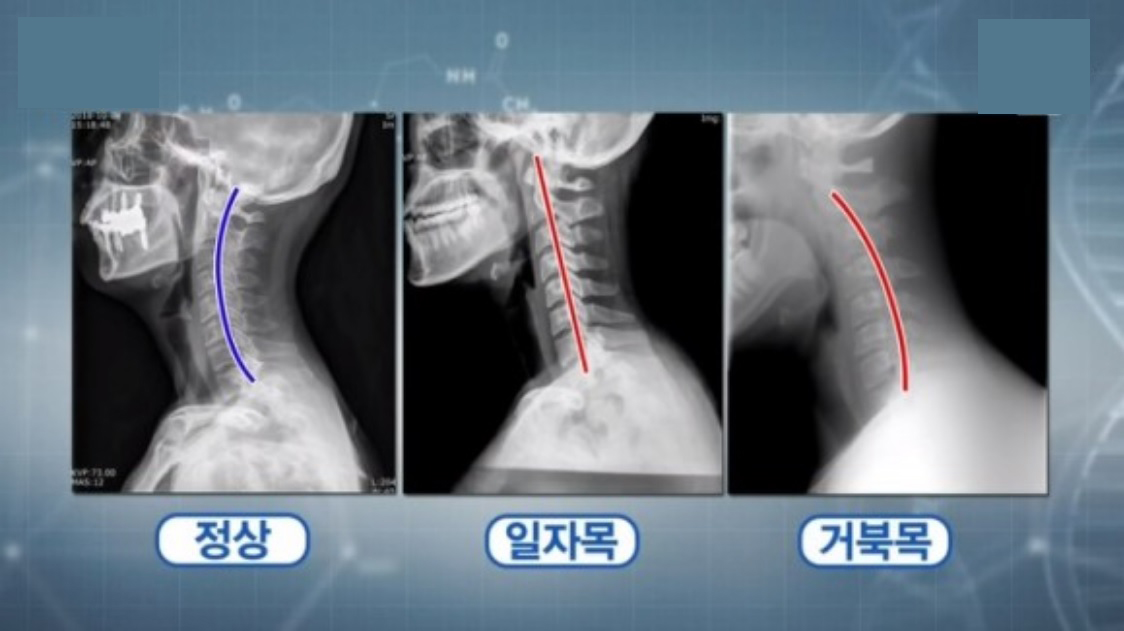

거북목은 저말고도 다른 학생 및 어른들도 자주 겪는 자세 문제 중 하나로, 허리와 목의 곡선이 퇴화되어 자세가 앞으로 구부러지는 상태를 말해요.

1. 거북목의 문제점과 통증 거북목은 잘못된 자세와 장시간의 스마트폰, 컴퓨터 사용으로 인해 발생할 수 있어요.

이로 인해 목과 어깨 근육의 긴장이 증가하고 척추의 곡선이 변형되어 통증을 유발할 수 있습니다.